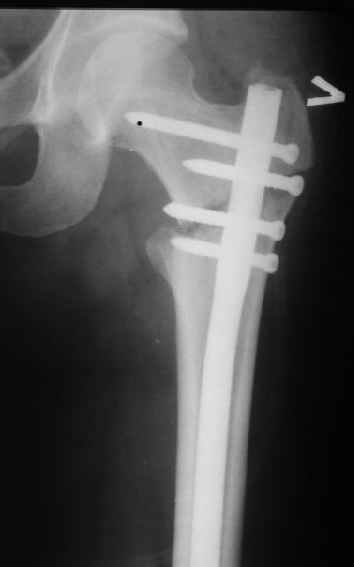

В частности, на проксимальном конце сделано еще одно дополнительное статическое отверстие. Можно ввести в проксимальном отделе 4 винта, из них 3 статические (2 в круглые отверстия и 1 по нижнему краю овального). Картинки в приложении. На дистальном конце стержня тоже кое-что улучшено. Спрашивайте в аптеках, как говорится. Выпускается предприятием "ЦИТО" (Москва), то есть это малобюджетное решение.

Могу скромно напомнить о существовании стержня нашей модификации.

Это было года 2,5 назад, мы тогда еще уточняли возможности шинирования с угловой стабильностью гвоздем с поперечным расположением винтов при переломах проксимального отдела бедра. Пациенту не пришлось приобретать намного более дорогой рекон или проксимальный гвоздь. В приложении еще несколько примеров применения того гвоздя при высоких переломах бедра, в том числе с более латеральной точкой входа. Гвоздь изгибаем для этого.